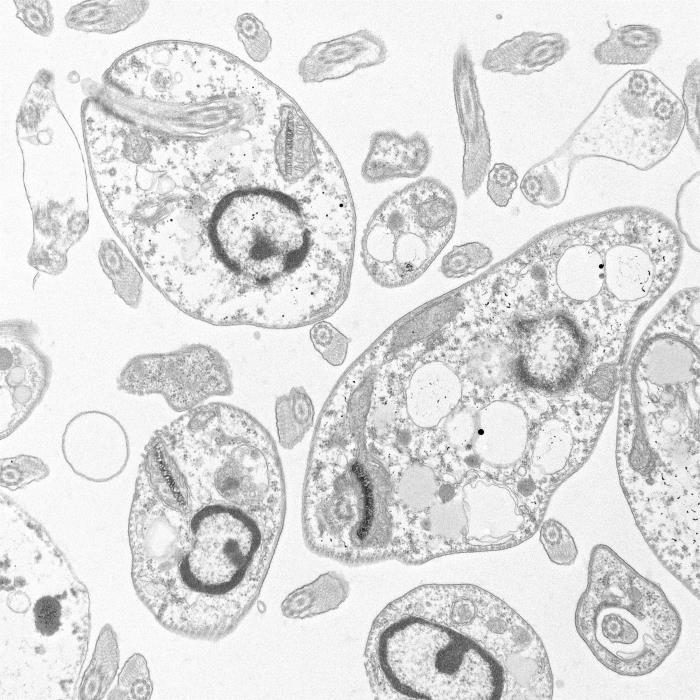

El complejo Leishmania tropica está constituido por parásitos protozoarios pertenecientes al filo Sarcomastigóforos, familia Trypanosomatidae. Se trata de organismos esféricos u ovales, con un solo núcleo en el citoplasma (cinetoplasto) y un tamaño aproximado de 1,5-2,5 x 3-6 micras. Son parásitos intracelulares obligados de muchos mamíferos, se alimentan por difusión del contenido del citoplasma de la célula hospedadora y se reproducen por fisión binaria.